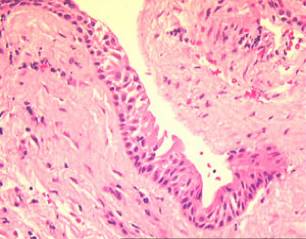

Гистологические изображения фолликулярной кисты яичника